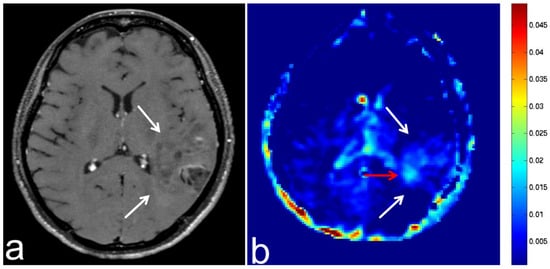

5.4. Malignant Lymphoma